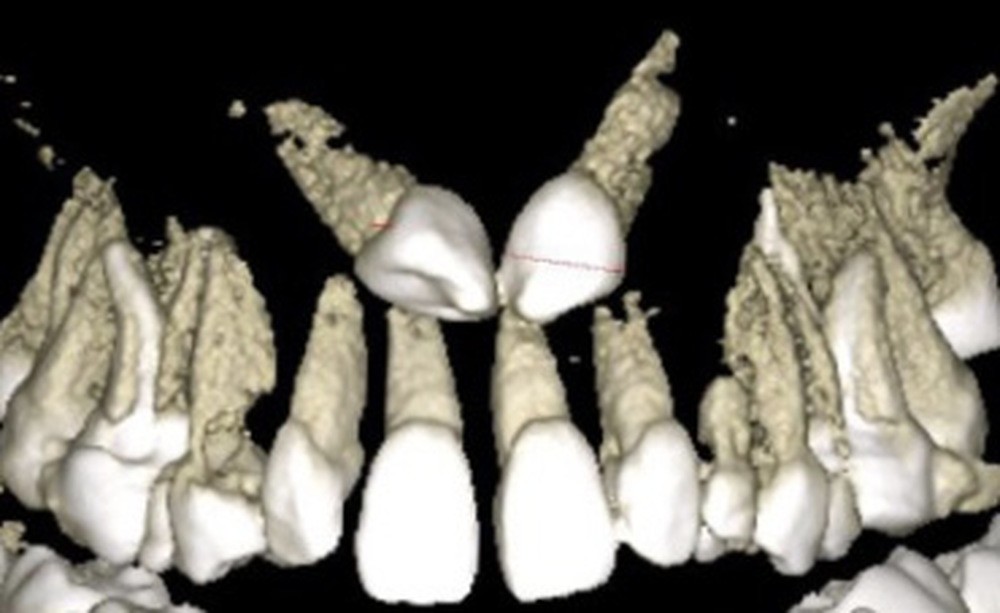

L’examen radiologique 2D nous confirme l’inclusion de 13 et 23 en position haute, oblique en bas et en avant, couronnes en projection des apex de 11 et 21 et nous permet de quantifier le décalage squelettique (fig. 3 et 4). L‘examen radiologique 3D (cone beam) objective les rapports…